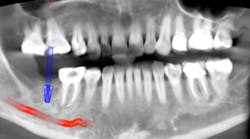

The old saying “you don’t know what you don't know” holds especially true in regard to 3-D radiology. You simply cannot gain the same amount of information from 2-D images. My main use for CBCT in the general dentistry practice is dental implant planning. In order to feel confident placing dental implants, I need this technology. I am able to identify cases that are appropriate for my skill level, as well as cases that are more difficult and should be referred. Whether a case will be tricky is not always obvious from a 2-D image and clinical exam. I also have not found a situation where less information was more beneficial than more information. I have never thought to myself, “I wish I didn’t have a 3-D scan of this patient.” Conversely, there were many times before buying my CBCT when I wished I had more than just a 2-D periapical (PA) or pan. The case shown in figures 1, 2, and 3 illustrates how the additional information CBCT provides aids in planning and placing dental implants.

Figure 3 tells a more complete story. The patient has a significant lingual concavity. I was unable to palpate the concavity clinically to realize its full extent. The 3-D image allows accurate measurement to the inferior alveolar nerve (IAN) and lingual concavity. It allows me to plan and place an implant of the appropriate length to avoid perforation of the lingual plate, which could lead to serious surgical complications.